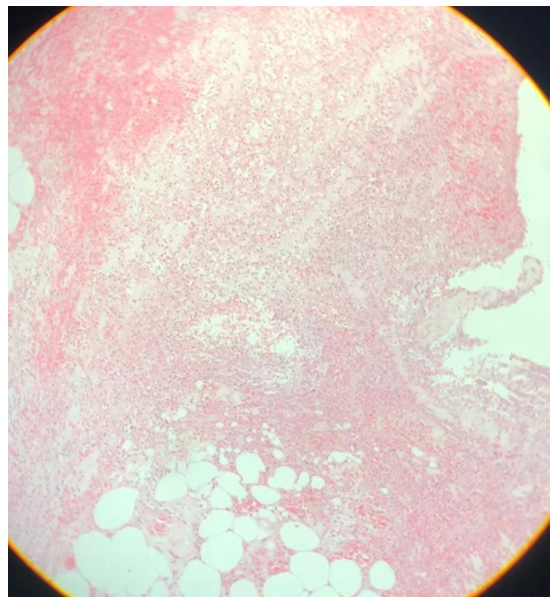

Achados Microscópicos: os cortes histológicos do apêndice revelaram extensa infiltração difusa de tecido adiposo maduro nas camadas da parede apendicular, caracterizando lipomatose (Figura 4). Os adipócitos apresentavam morfologia completamente diferenciada, sem atipias ou figuras de mitose, e estavam envolvidos por finas traves de estroma fibroso, sem formação de cápsula circunscrita. Adicionalmente, observou-se na superfície serosa um denso infiltrado inflamatório agudo neutrofílico associado a depósito fibrinoso, configurando uma serosite fibrinoleucocitária (Figura 3 e Figura 5). Importante notar que não havia comprometimento inflamatório significativo da mucosa ou submucosa – achado compatível com periapendicite ou apendicite serosa. Não se identificaram áreas de atipia celular, necrose ou padrão lobular que sugerissem transformação maligna em lipossarcoma. Com base nesses achados, concluiu-se o diagnóstico de lipomatose do apêndice cecal associada à serosite fibrinoleucocitária. Foram produzidas lâminas representativas das lesões observadas (Figura 6).

Coloração HE, aumento 40x. Fonte: autoria própria.